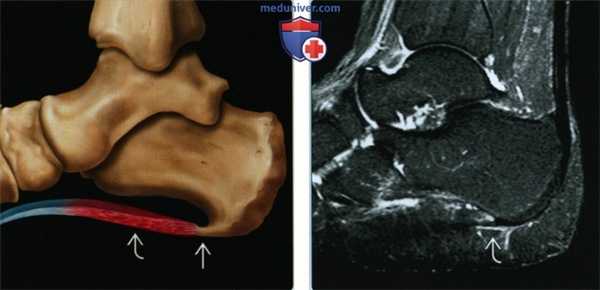

(Левый) На рисунке показан воспалительный процесс в подошвенной фасции, проявляющийся утолщением ее центральной порции. Также на подошвенной поверхности пяточной кости изображен костный вырост, однако его наличие не является достоверным признаком фасциита. Костные выросты пяточной кости во многих случаях анатомически не связаны с подошвенной фасцией.

(Правый) При МРТ в сагиттальной плоскости в режиме STIR визуализируются слабо выраженные признаки подошвенного фасциита минимальное утолщение фасции и отек тканей над фасцией и под ней.